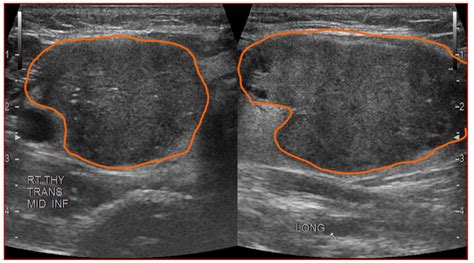

Very hypoechoic thyroid nodule. It may indicate fluid, tissue changes, or potentia...

Very hypoechoic thyroid nodule.  It may indicate fluid, tissue changes, or potentia...Very hypoechoic thyroid nodule.  It may indicate fluid, tissue changes, or potentia...